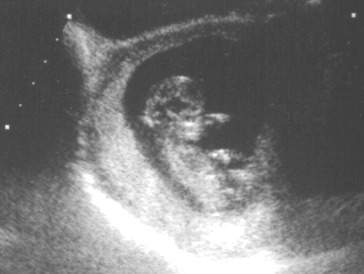

One of the main questions of expectant mothers at this point is how their babies have developed at this stage of pregnancy. Various organ systems of the baby have also began to develop like the digestive system. Furthermore, fetus will also start to look more like a baby at this stage instead of just being a fertilized egg cell. Brain and nerve systems also continues to develop. Heartbeats are also audible at this stage so it will excite more expectant mothers in the process.